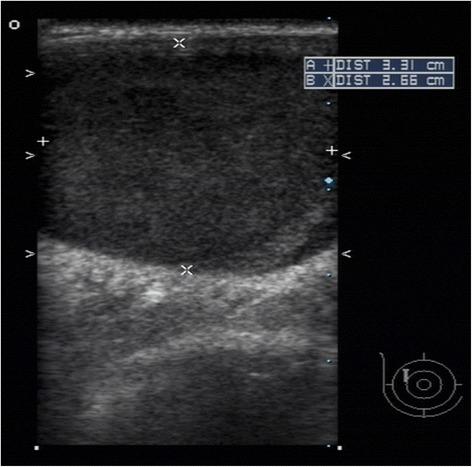

We describe an 83-year-old Taiwanese woman with a metastatic thymoma to the breast 10 years after complete resection of noninvasive and encapsulated primary tumor, and analyze the possible factors to explain the recurrence and metastasis of the stage I thymomas.

我们描述了一名83岁的台湾女性,在无创性包膜原发性肿瘤完全切除10年后发生了胸腺瘤转移至乳腺的情况,并分析了解释I期胸腺瘤复发和转移的可能因素。